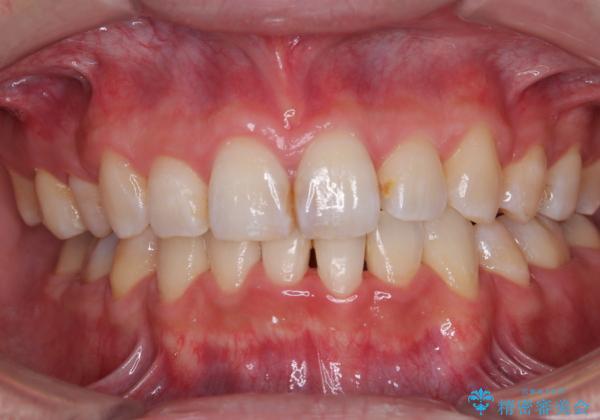

顎が左右にずれた咬み合わせ ハーフリンガルの抜歯矯正

- 口元の突出感を気にして来院された患者様です。

上下の顎骨が左右に大きくずれており、奥歯が交叉咬合となっていたため、ハーフリンガルよりも表側装置をおすすめしましたが、目立たない装置を強く希望されたため、治療期間が長期化することを前提に、ハーフリンガルにて抜歯矯正を行うこととしました。